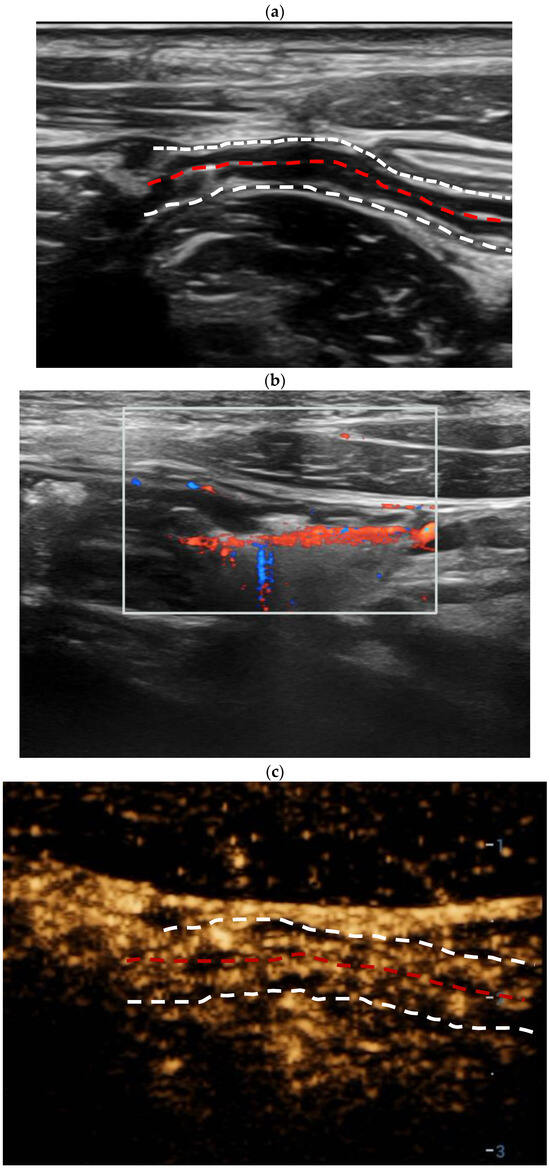

| Color Doppler signal | <0.001 * | ||

| Limberg 0 | 0 | 6 (46.1%) | |

| Limberg I | 5 (12.8%) | 3 (23.1%) | |

| Limberg II | 22 (56.4%) | 4 (30.8%) | |

| Limberg III | 7 (18.0%) | 0 | |

| Limberg IV | 5 (12.8%) | 0 | |

| CEUS enhancement | <0.001 * | ||

| Pattern I | 24 (61.5%) | 1 (7.7%) | |

| Pattern II | 10 (25.6%) | 3 (23.1%) | |

| Pattern III | 5 (12.8%) | 8 (61.5%) | |

| Pattern IV | 0 | 1 (7.7%) | |